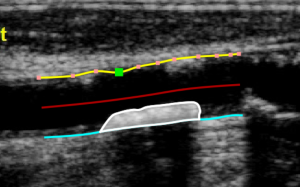

After the two borders are traced, the software automatically compute the minimum and maximum values of the diameter and the linear and circular values of the stenosis. The Draw plaque  button is used to manually draw the profile of a plaque. The user has to trace point-by-point the plaque profile and the software interpolates them. Also in this case, it is possible to modify the points by dragging them and to delete a plaque, as shown in the following picture.